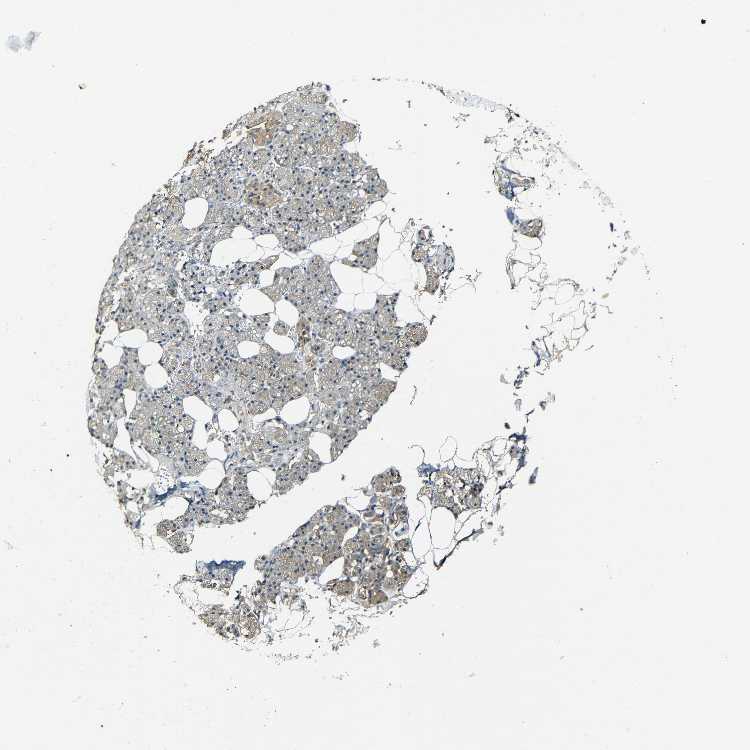

SALIVARY GLAND - Antibody stainingi

Antibody staining in the annotated cell types in the current human tissue is reported as not detected, low, medium, or high, based on conventional immunohistochemistry profiling in selected tissues. This score is based on the combination of the staining intensity and fraction of stained cells.

Each image is clickable and will lead to virtual microscopy that enables deeper exploration of all samples and also displays staining intensity scores, fraction scores and subcellular localization as well as patient and tissue information for each sample.

Antibody HPA001302Antibody HPA005688Antibody CAB002047

Glandular cells MediumHighLow